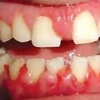

Gingiviit ehk igemepõletik

(Gingivitis)

Gingiviit on hammast ümbritseva igeme põletikuline protsess, mis on tingitud hambakatu kogunemisest ning mis kujuneb välja ebasoodsate lokaalsete ja üldiste faktorite toimel, kusjuures on säilinud igeme terviklik kinnitus hambapinnale ja...

Krooniline gingiviit

Krooniline gingiviit, mida seostatakse katu kogunemisega, esineb enamasti ja on väga tavaline täiskasvanud populatsioonis ning kujuneb välja peale 2-3 nädalast katu ladestumist igemepiirile. Nii nagu on erinevad kõik inimesed on...